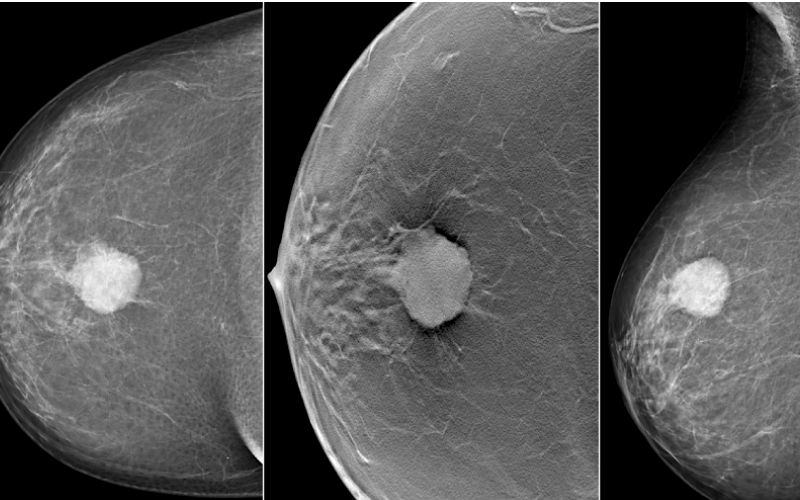

- ماموگرافی سینه: تصویربرداری با اشعه ایکس از بافت سینه برای شناسایی تودهها.

سونوگرافی و ماموگرافی از دقیقترین و بهترین راه های تشخیص سرطان سینه هستند. در برخی موارد، برای تأیید تشخیص، بیوپسی یا نمونهبرداری از توده و بررسی پاتولوژیک نیز لازم است. اما اولین اقدام پس از تشخیص توده پستان استفاده از روش های هدایت تصویربرداری است از جمله:

سونوگرافی سینه: این روش تصویربرداری میتواند حتی کوچکترین ناهنجاریها را در سینههای متراکم شناسایی کند و به تعیین اینکه توده کیست یا جامد است، کمک میکند.

ماموگرافی سینه: ماموگرافی دیجیتالی تصاویر واضحی از پستانها ارائه میدهد و میزان تابش کمتری دارد. رادیولوژیست این تصاویر را تحلیل میکند تا محل و میزان بیماری را تعیین کند.

شکل توده سینه در سونوگرافی

در صورت وجود توده در سینه، در تفسیر نتایج سونوگرافی ناحیه ای کاملا مشخص و با تضاد رنگی نسبت به ناحیه اطراف مشخص میشود که دارای پژواکهای افزایش یافته (سفیدتر) در عمق توده است. این ناحیه دارای لبه های واضحی است.